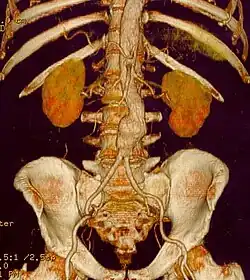

Als Bauchaortenaneurysma (BAA), abdominales Aortenaneurysma (AAA) oder Aneurysma verum aortae abdominalis wird eine Erweiterung der abdominalen Aorta unterhalb des Abgangs der Nierenarterien im anterioposterioren Durchmesser auf über 30 mm angesehen. Klinisch unterscheidet man zwischen asymptomatischen, symptomatischen und rupturierten Aneurysmata. Beim asymptomatischen (schmerzfreien) Aneurysma handelt es sich um einen Zufallsbefund. Beim symptomatischen Aneurysma stehen die Symptome und bei den rupturierten die Kreislaufsituation im Vordergrund.

- Die Computertomographie gilt derzeit als Goldstandard zur Untersuchung eines AAA. Sie ist zwar mit einer Strahlenbelastung für den Patienten behaftet, kann aber sehr gut zur Größenbestimmung verwendet werden und die räumliche Ausdehnung des Aneurysmas zeigen. Auch Verkalkungen und evtl. schon eingesetzte Stents können untersucht werden. Moderne CTs liefern auch Bildrekonstruktionen, die zur OP-Planung eingesetzt werden können.